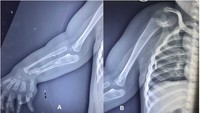

Berdasarkan hasil pemeriksaan, terlihat adanya pengecilan otot yang nyata di sekitar bahu dan skapula, disertai tidak adanya gerakan aktif pada abduksi, fleksi, maupun rotasi bahu. Siku dalam posisi fleksi 30 derajat tanpa kemampuan melakukan supinasi maupun pronasi. Lengan bawah dan pergelangan tangan tampak melebar.

Selain itu, rontgen tangan menunjukkan duplikasi tipe III pada jari tengah, duplikasi tipe V pada jari manis, jari kelingking yang mengalami deviasi ulnar, serta pergelangan tangan dengan tiga tulang. Sementara itu, anggota gerak atas kiri, wajah, tulang belakang, panggul, dan ekstremitas bawah tampak normal. Pasien tidak mengalami obesitas, dan hasil parameter darah berada dalam batas normal.Foto: jurnal PlumX Metrics